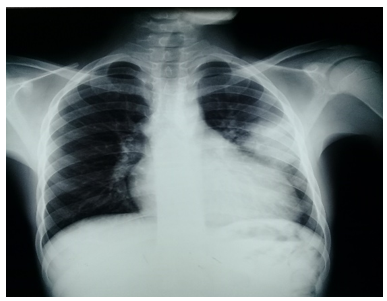

El estudio imagenológico mediante radiografía de tórax postero anterior inicial mostró la existencia de una imagen heterogénea de aspecto inflamatorio con proyección al tercio medio del hemitórax izquierdo: cardiomegalia (figura 1).

Figura 1. Radiografía de tórax en vista postero anterior

Fuente: historia clínica del paciente.